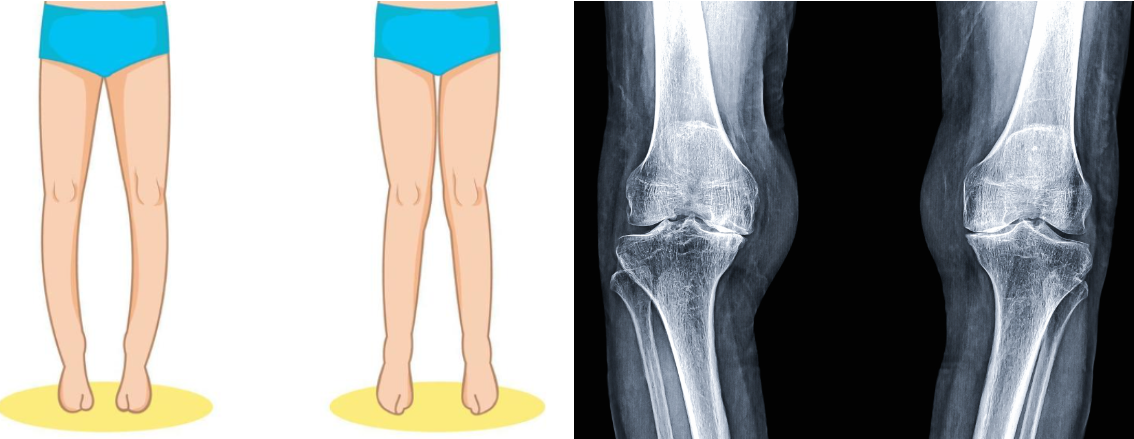

무릎 인공관절 수술은 Total Knee Replacement, TKR 혹은 Total Knee Arthroplasty, TKA라고 합니다. 'O'형 다리나 'X'형 다리에서 60대가 넘어갈수록, 체중이 많이 나갈수록 관절 연골이 심하게 닳을 수 있습니다.

오형 다리에서는 무릎 안쪽 연골이 닳고 엑스형 다리에서는 무릎 바깥쪽 연골이 닳아 통증으로 연결되고 절뚝거리며 계단 오르내리기가 힘들게 됩니다.